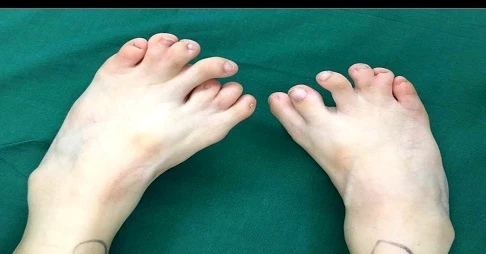

Hình ảnh ghi lại chân một bé gái Trung Quốc 4 tuổi bị dị tật bẩm sinh có 13 ngón, chân trái của bé có 7 ngón, chân phải 6 ngón. Kể từ khi được sinh ra, cha mẹ bé đã sống trong sự đau khổ vì lo lắng dị tật sẽ tiếp tục biến chứng, cùng với đó là sự nhạo báng của miệng lưỡi người đời.

Không chỉ sở hữu số ngón chân nhiều bất thường, bàn chân của bé gái còn mở to biến dạng, ảnh hưởng đến đi lại. Mẹ bé cho biết, ngay cả những đôi giày bình thường bé cũng không thể đi vừa. Sau khi kiểm tra kỹ lưỡng, các bác sỹ kết luận, dị tật bàn chân trong trường hợp lần này khá hiếm gặp, vậy nên Phó giám đốc bệnh viện Bắc Kinh đã trực tiếp tham gia vào cuộc phẫu thuật chỉnh hình.

Đầu tháng 8 vừa rồi, cha mẹ bé gái đưa con họ tái khám, các bác sỹ vui mừng thông báo chân của bé gái đã phục hồi và hoạt động bình thường, không có vấn đề gì xảy ra.